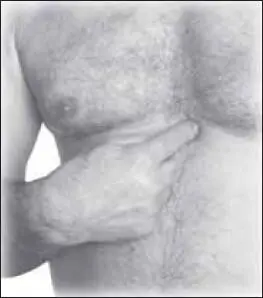

Сердечные заболевания

Сердечные боли могут возникнуть вследствие чрезмерных физических нагрузок, стресса. Ощущается скованность, тяжесть и давление в области грудной клетки. Иногда боль отдается в левую руку, плечо. Необходимо в первую очередь принимать лекарство, назначенное врачом.

Воздействие седативное, расслабляющее, медленное, успокаивающее (1–2 минуты). Начинают с точки цзю-вэй (расположена на средней линии груди ниже конца мечевидного отростка грудины, на 7 цуней выше пупка вверх по средней линии) (рис. 129).

Затем воздействуем на точку чжоу-жун (расположена во 2-м межреберье на расстоянии 6 цуней от средней линии груди) (рис. 130).